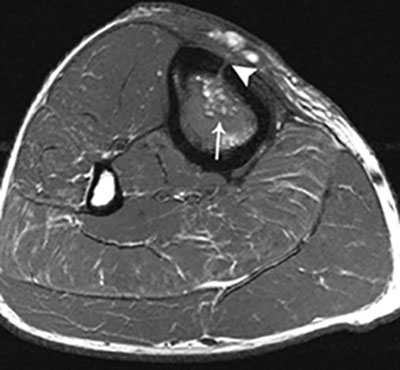

Fat globule sign on T1–WI. Axial T1–WI showing fat globules (white arrow) within the bone marrow edema of the tibia. In addition, there is a cortical defect – also known as the cloaca – perforating the ventromedial cortex of the tibia (white arrowhead).

Magnetic Resonance Imaging is the modality of choice for early detection of acute OM. Bone marrow changes are detected within three to five days after disease onset on Fat–Sat T2-weighted imaging (WI). OM can spread to the joint depending on the position of the joint capsule compared to the growth plate. An extra-articular location of the growth plate does not predispose to joint infection, whereas intra-articular position of the growth plate may cause rapid spread to the adjacent joint (Figure 8). Soft tissue extension, joint effusion, abscess formation and sinus tracts are accurately visualized. A pathognomonic sign for acute osteomyelitis is the presence of intramedullar fat globules on T1–WI. Islands of fat are released by necrotic lipocytes resulting in high signal intensity (SI) on T1–WI (Figure 9) [8910].